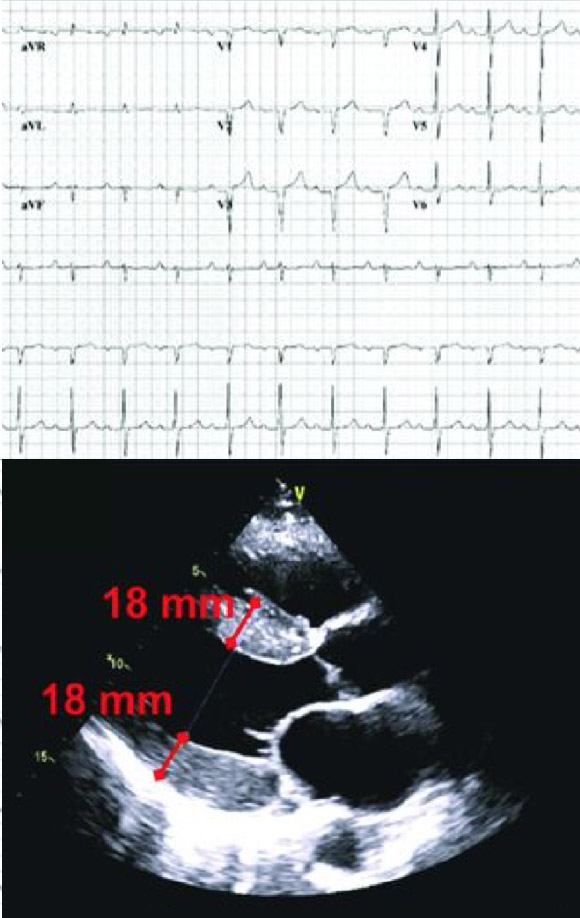

- În ATTR-CM, funcţia diastolică este afectată de depozitele de amiloid din miocard, care determină îngroşarea şi rigidizarea ventriculilor şi implicit debitului cardiac. Abia în stadiile mai avansate de evoluţie a ATTR-CM survine scăderea fracţiei de ejecţie8, 9

- Indiciile imagistice, precum reducerea strainului longitudinal cu sparing pe segmentul apical, pot creşte suspiciunea clinică1, 9